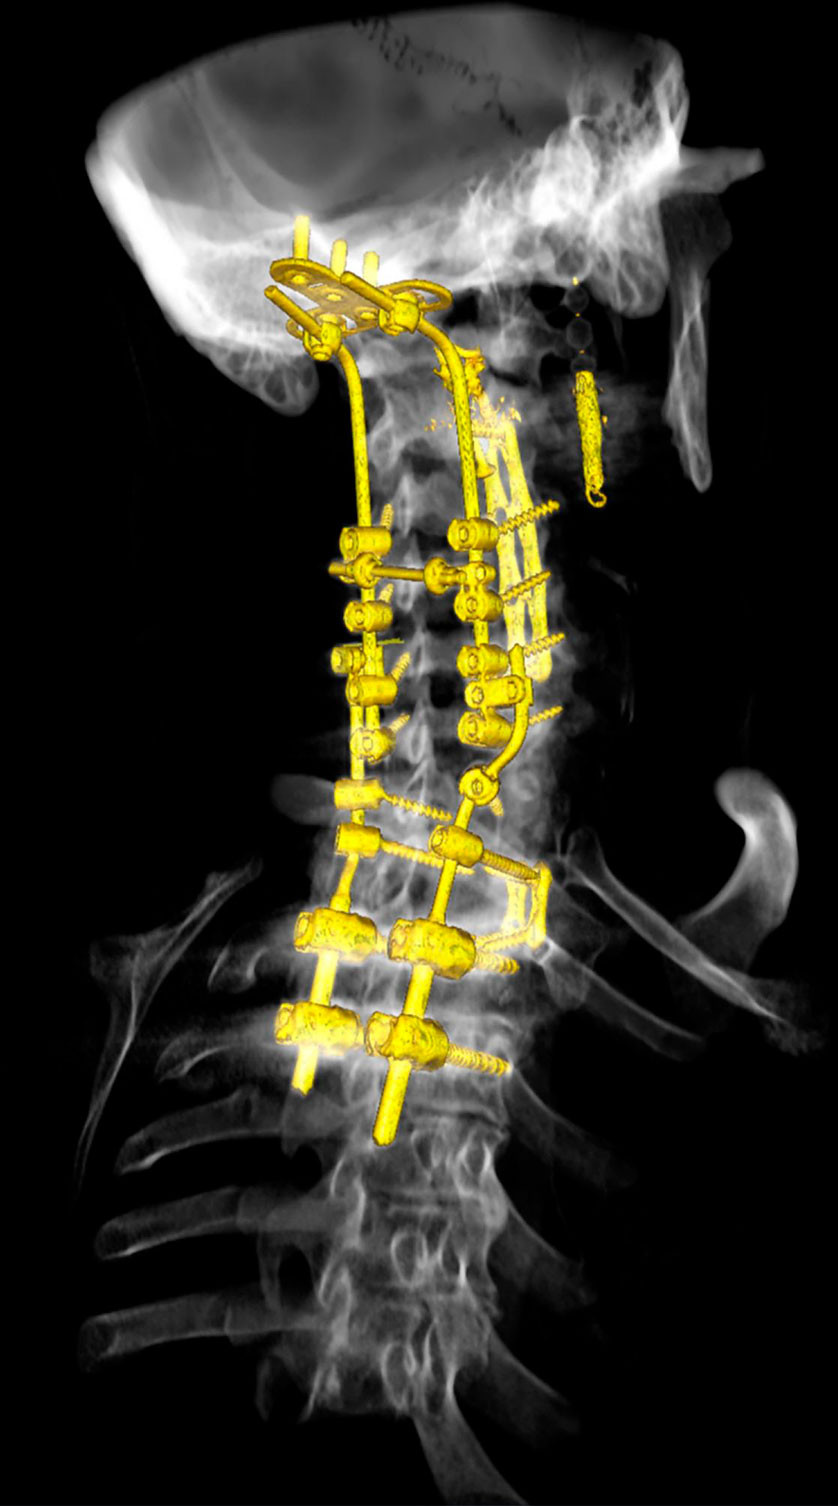

Etter diskusjon med infeksjonsmedisinere og nevrokirurger ble det funnet indikasjon for operasjon med bakre fiksering med bruk av ben fra ribben ned til Th3 (figur 4). Dette ble gjort i narkose, og det ble også gjennomført korpektomi av C6, C7 og Th1 og tatt nye benbiopsier (dag 281). Pasienten stod på dette tidspunktet på monoterapi med peroral isavukonazol (200 mg × 1 daglig). Behandlingen med intravenøs anidulafungin (100 mg × 1 daglig) ble gjeninnsatt og behandlingen med isavukonazol per os kontinuert. Konsentrasjonen av isavukonazol lå i flere prøver på terapeutisk nivå, og minste hemmende konsentrasjonsverdier for både isavukonazol og anidulafungin for A. flavus var lave.

Etter to og en halv ukes rehabilitering i kommunal institusjon, ble pasienten skrevet ut til hjemmerehabilitering i regi av kommunen. Etter kort tid fikk han på ny økende nakkesmerter med utstråling til venstre arm og ben. Han hadde problemer med å holde hodet oppe og gikk med flektert nakke. Pasienten ble reinnlagt (dag 276), og ny CT-undersøkelse (figur 3) viste brudd i processus spinosus på C6 og destruksjon i corpora av C6–C7 og Th1. Det var også mistanke om en lesjon i Th3.